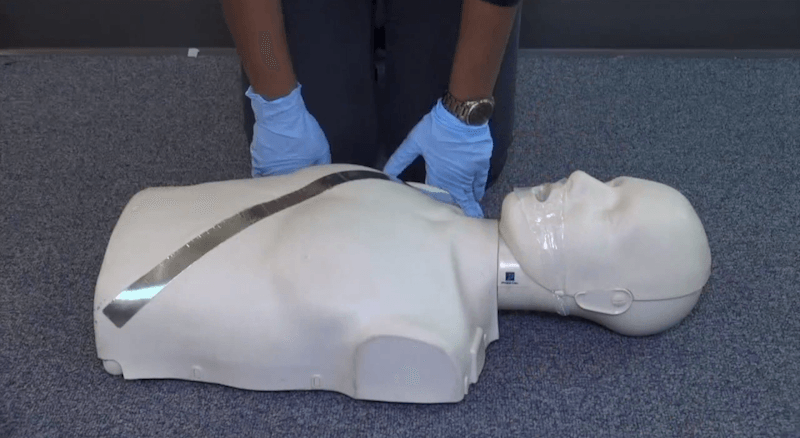

CPR SIMULATOR INSTRUCTIONS

- Click the mouse on the chest to apply compressions. (30 compressions per cycle at 100-120 beats per minute)

- Hold the mouse on the mouth to apply breaths. (2 per cycle, hold button for approx 1 second each breath)